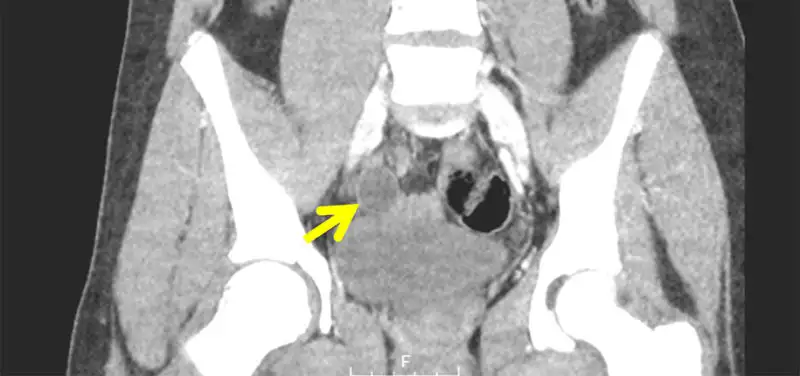

Image: CT image of appendicitis, marked by yellow arrow

If this is the case, we may rely on other signs of inflammation in the abdomen that can be seen by ultrasound, such as enlarged lymph nodes or an abnormal appearance of the normal abdominal fat, to suggest that your child has appendicitis. If the ultrasound is indeterminate and the emergency room doctors or surgeons remain concerned for appendicitis, they may order a CT scan. A CT often allows a better look at the appendix, but it is considered a secondary option for children because of its use of radiation to create an image.

In the end, ultrasound and CT are complementary options for imaging a child suspected of having appendicitis. Both are effective tools that help us to identify the appendix, and, when combined with the evaluation of your emergency room doctors and surgeon, diagnose appendicitis.